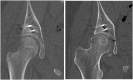

Case: We present the case of a thirteen-year-old female who sustained a posterior wall acetabular fracture dislocation. She underwent urgent closed reduction and subsequent uncomplicated open reduction and internal fixation. Post reduction computed tomography demonstrated a concentrically reduced hip joint with no evidence of femoroacetabular impingement (FAI). She subsequently healed her fracture and returned to running activities; however, one year later presented with aching pain in her thigh. Radiographs demonstrated the development of a large osseous prominence on her anterolateral femoral neck consistent with femoroacetabular impingement. Based on these findings she was evaluated by a hip preservation specialist. She subsequently underwent successful hip arthroscopy for labral repair and femoral osteochondroplasty. She was eventually able to return to running sports with little pain.

Summary: We present a case of FAI presenting as a complication of acetabular fracture fixation. This should be discussed with patients presenting with traumatic hip dislocations as a possible complication of surgical fixation or possibly of the injury itself.